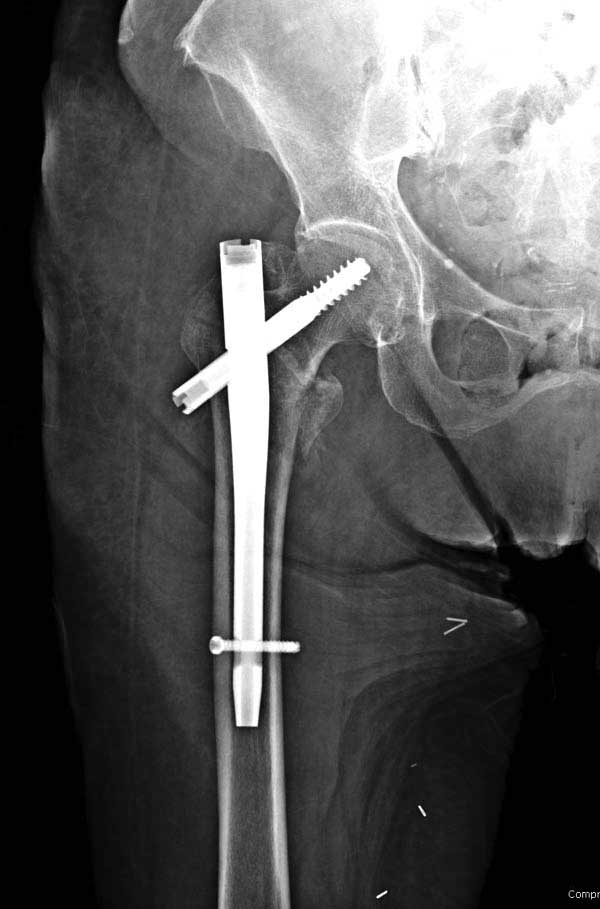

Повторно поступает после двух с половиной лет, где обнаруживается перелом на второй стороне. Немного сложно, но для фиксации выбрали Antegrade InterTan Smith Nephew Nail и с момента фиксации более 3х мес.

Имя     : 35 IT fx LT injury CRM3 final.JPG

Тип     : image/jpg

Размер  : 27796 байтов

Описание: отсутствует

Url     : http://weborto.net:8080/pipermail/ortho/attachments/20120509/52aada75/attachment-0055.jpg